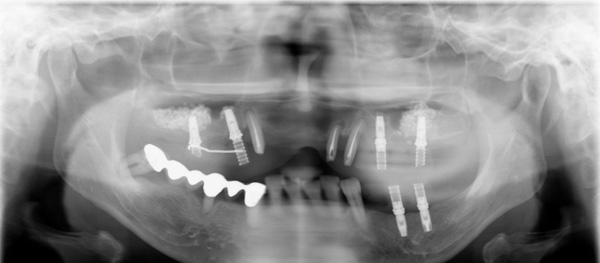

プロビジョナルレストレーションに置き換え、適正な咬み合わせに調整しています。

上顎奥歯のインプラント治療はサイナスリフト(骨造成)をおこないました。